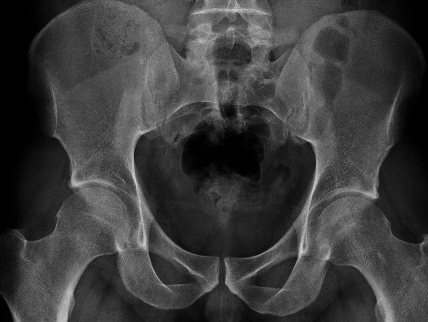

Bilateral pincer

Ossified labrum

Os acetabuli